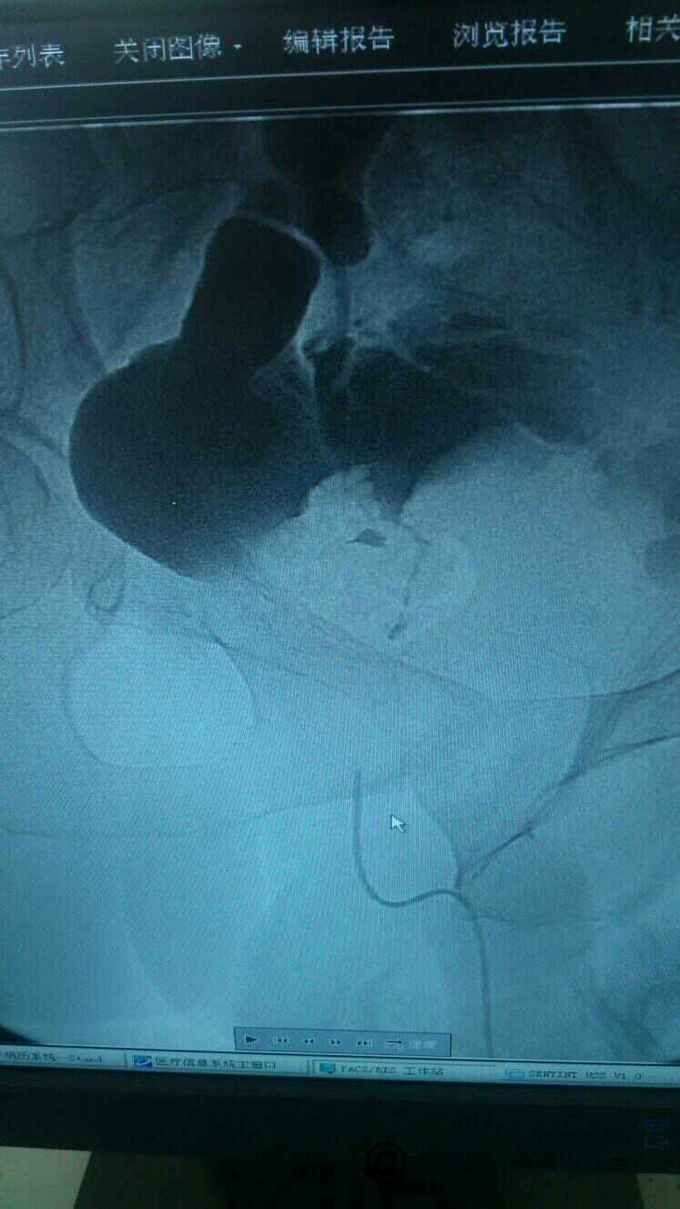

查膀胱镜发现后尿道狭窄,无法进入膀胱。 尿道造影:尿道狭窄,输尿管逆流。嘱咐病人排尿时,膀胱内尿液减少,进入输尿管,肾盂。 肾功能正常。

诊断:尿道狭窄,输尿管逆流 治疗:输尿管镜下探查,见尿道狭窄,膀胱内景清晰,广泛房小梁形成,右侧膀胱后壁可见广口凹陷,输尿管镜置入,可向上探查,实为输尿管,管腔宽大,输尿管镜进出自如,未见占位病变,向膀胱内置入导丝,沿着导丝留置导尿管扩张尿道。